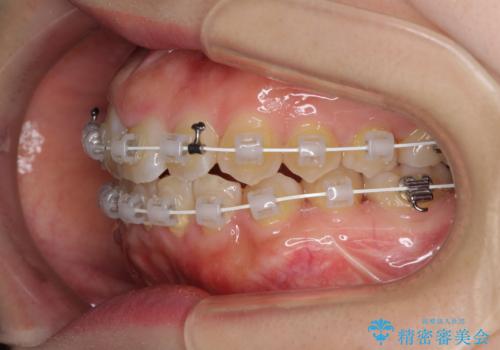

- 矯正装置

- 審美装置

- 治療期間

- 2年

- 治療回数

- 10-30回